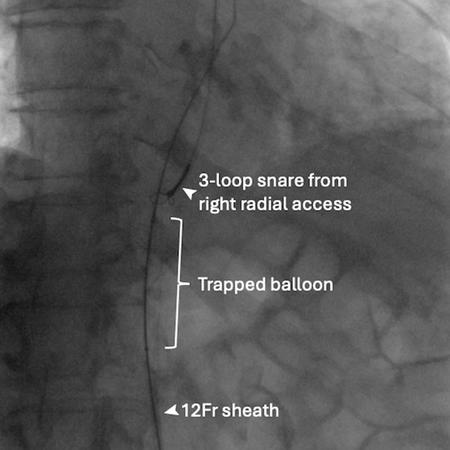

Physical withdrawal of the unsheathed deflated balloon was considered and briefly attempted but was resisted, and severe damage to the calcified iliac and femoral systems was feared. Snaring of the balloon tip from the right radial access for straightening the system did not help with retrieval (Figure 1B).

Figure 1B: Snaring from right radial access.